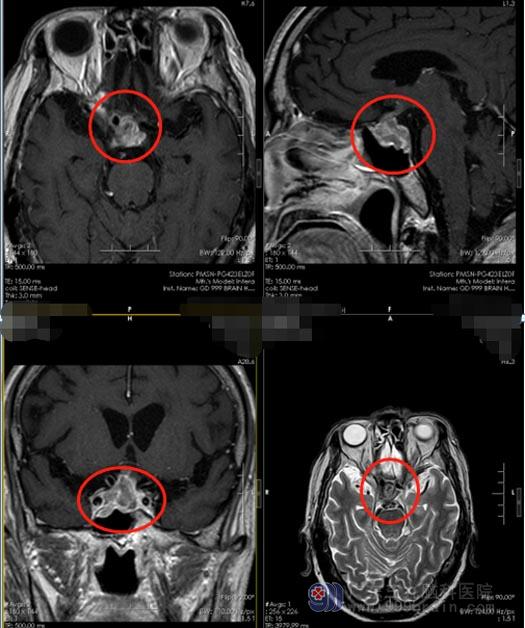

80岁的李爷爷在半个月前突然出现头疼、左眼视力下降。家人立即带他在当地医院行头部磁共振检查,结果提示:鞍区垂体瘤并卒中。广东三九脑科医院副院长、神经外五科主任鲁明仔细查看了患者的影像检查资料,发现李爷爷的颅内肿瘤出血,并压迫视神经引起视力的下降,眼睛已经完全失明。

垂体瘤是颅内最常见良性肿瘤,生长于垂体窝内,分为有功能和无功能分泌两种类型,部分肿瘤患者是由于出现剧烈头痛和视力下降就诊。垂体瘤卒中是指垂体瘤在短期内瘤体出血,导致肿瘤体积迅速扩大,对周围神经结构造成压迫,出现视力下降以及头疼症状。